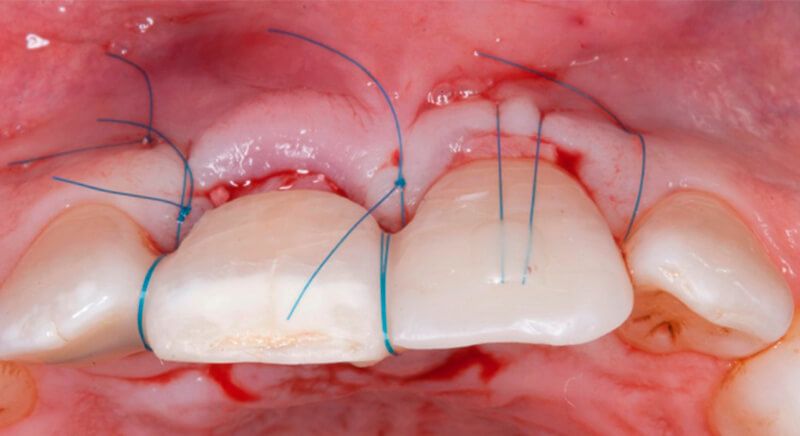

The socket was filled with a xenograft after the extraction and a graft of connective tissue was placed in the vestibular area of the two upper central incisors.

The tissue with epithelium was taken from the palate and de-epithelialized outside of the mouth. This obtains a lamina propria graft with better density and quality than if it were obtained with a single incision to the palate.